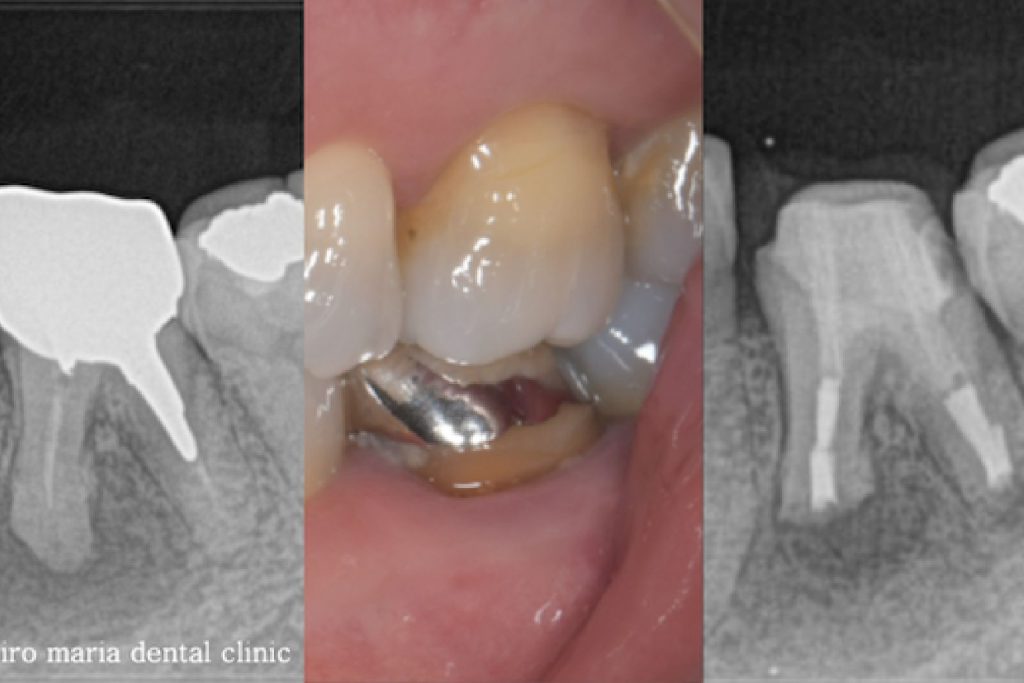

右上の奥歯付近に“できもの”ができたことを主訴に来院された患者様の症例です。当院での診査の結果、右上7番の根尖性歯周炎と診断しました。しかし、一部に限局的に進行している歯周ポケットが確認できたため、歯根破折もしくは歯内歯周病変が疑われました。患者様は診断的な意味合い(歯根破折の確認)も含め、被せものを外して精密根管治療を開始することを希望されました。

精密根管治療の開始後、根管内充填物(感染物)を除去して根管内を確認すると、歯根破折が見られました(中央写真の赤矢印)。歯根破折は根管内に留まっていましたが、歯周ポケットと繋がっていたため、1回目の治療を中止しました。

上記のエックス線写真で、術直後に根尖付近に見られた透過像(黒く見える部分)は、3ヶ月後には小さくなり、治癒傾向にあることが確認できます。また、術前に見られた歯周ポケットの改善と瘻孔(フィステル)の消失も確認できます。